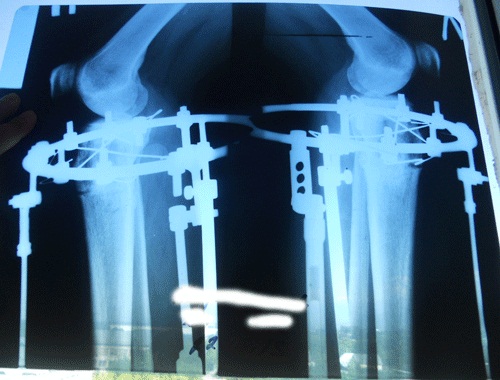

Рентген перед снятием аппаратов от 23 июня.

Вложения

2.JPG

1.JPG